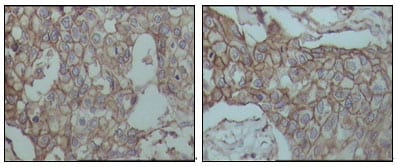

Immunohistochemical analysis of paraffin-embedded human breast carcinoma tissues, showing membrane localization with DAB staining using CD44 mouse mAb.